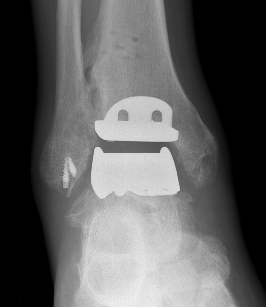

Infinity implant STAR implant Inbone

Agility Salto Tolaris Trabecular metal

3rd generation implants

- minimal bony resection with uncemented implants

- talus resurfacing with smooth surface

- +/- stems or pegs

- highly crosslinked polyethelene implant - mobile bearing versus fixed bearing